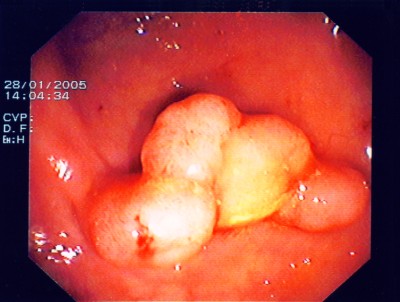

Wie bei den Abbildungen 28 und 30 handelt es sich um einen breitbasigen, relativ flachen, noch nicht entarteten Polyp, der sich mit einer Schlinge nicht vollständig abtragen ließe.

Wie bei den Abbildungen 29 und 31 erfolgt hier nach einem speziellen kombinierten Manöver (laparasko typisch gestützte Koloskopie - gleichzeitige Bauch- und Darmspiegelung), Entfernung des Polypen weit im Gesunden mit einem speziellen Klammernahtgerät. Die hier gut abgebildete Klammernahtreihe bleibt zurück. Der Eingriff erfolgt - wie gesagt - in so genannter Schlüssellochtechnik, aber auch mit unterstützender Darmspiegelung.